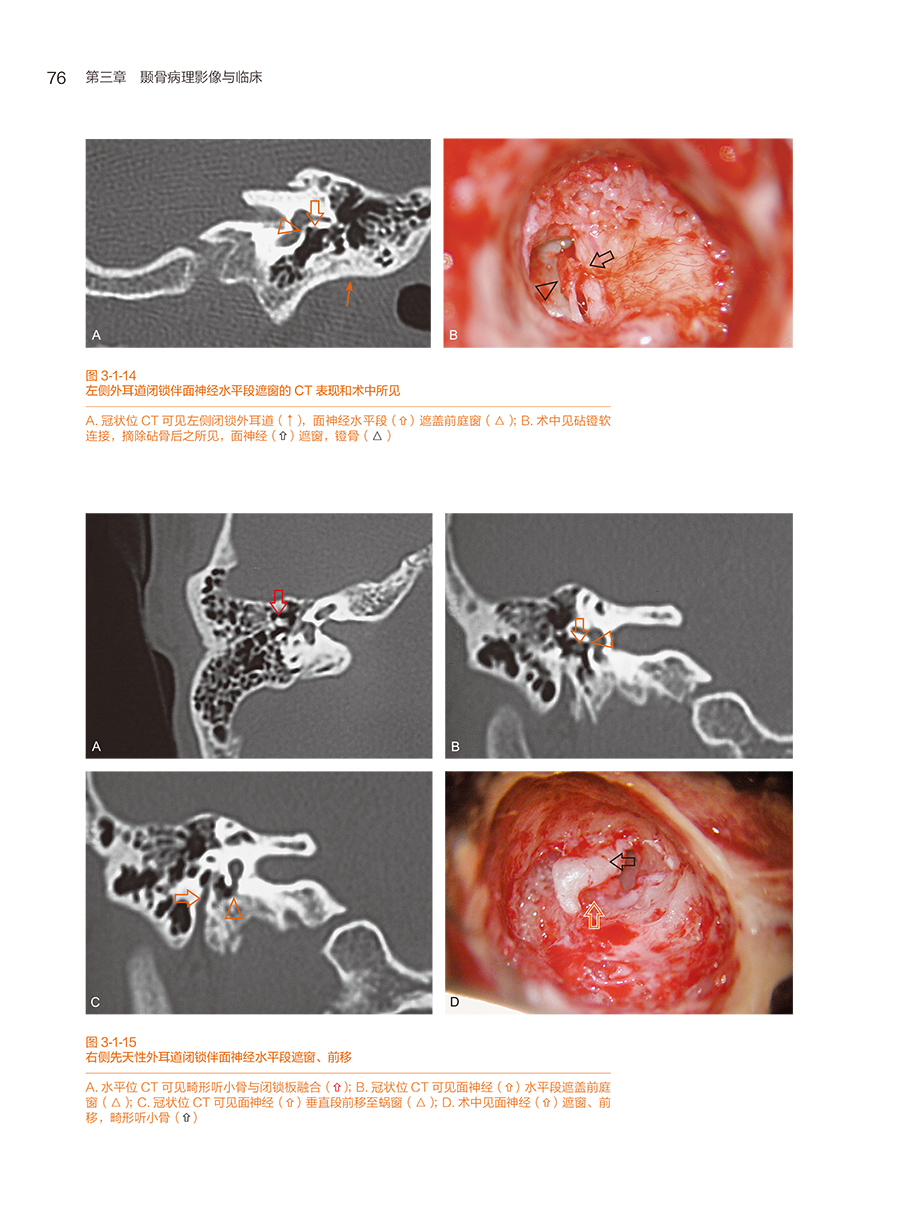

第一节 先天性颞骨畸形及解剖变异

一、先天性外耳道闭锁(或狭窄)伴中耳畸形及术后并发症